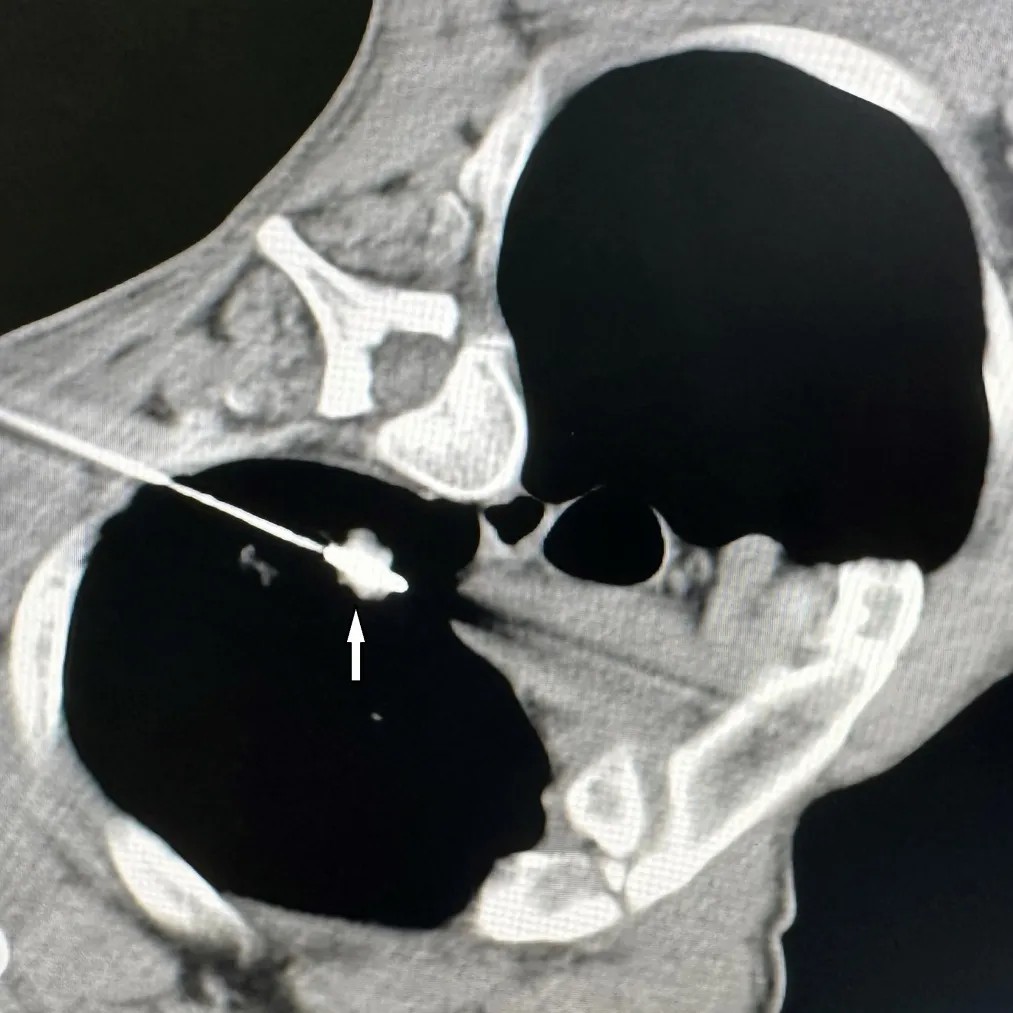

胸部CT显示肺上病灶一个位于肺上叶,因病灶位置较高,肋间隙较窄,比邻肩胛骨,给穿刺造成明显困难;另一个病灶紧邻主肺动脉,穿刺出血风险极高。7月25日,李建军主任经过仔细读片,认真分析,选择了最佳的穿刺路径,通过CT引导,在次旺晋美医师辅助,扎西次仁和德吉卓嘎护士配合下,一次手术对两个病灶进行了精准消融,术后CT扫描显示病灶完全坏死,未出现气胸等并发症,患者安返病房。

微波天线精准穿刺入肺上叶病灶内(白色箭头)